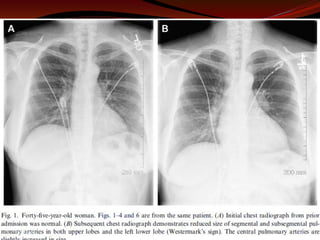

Chest Radiography

 Useful to R/o other causes

 Non specific findings; pleural Effusion, atelectasis,

consolidation

Classic sign

 Focal oligemia (Westermark sign) indicates massive

central embolic occlusion.

 A peripheral wedge-shaped density above the diaphragm

(Hampton hump) usually indicates pulmonary

infarction.

 Subtle abnormalities suggestive of PE include

enlargement of the descending right pulmonary artery.